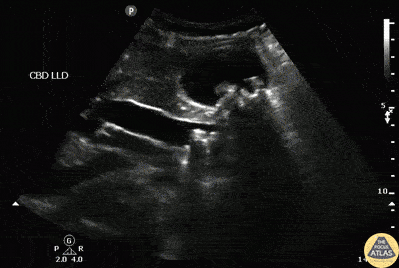

Biliary - Choledocolithiasis

A patient presented to the ED with RUQ pain. Sagittal view of the common bile duct revealed dilation and stones indicative of choledocolithiasis. Image courtesy of Robert Jones DO, FACEP @RJonesSonoEM Director, Emergency Ultrasound; MetroHealth Medical Center; Professor, Case Western Reserve Medical School, Cleveland, OH View his original post here